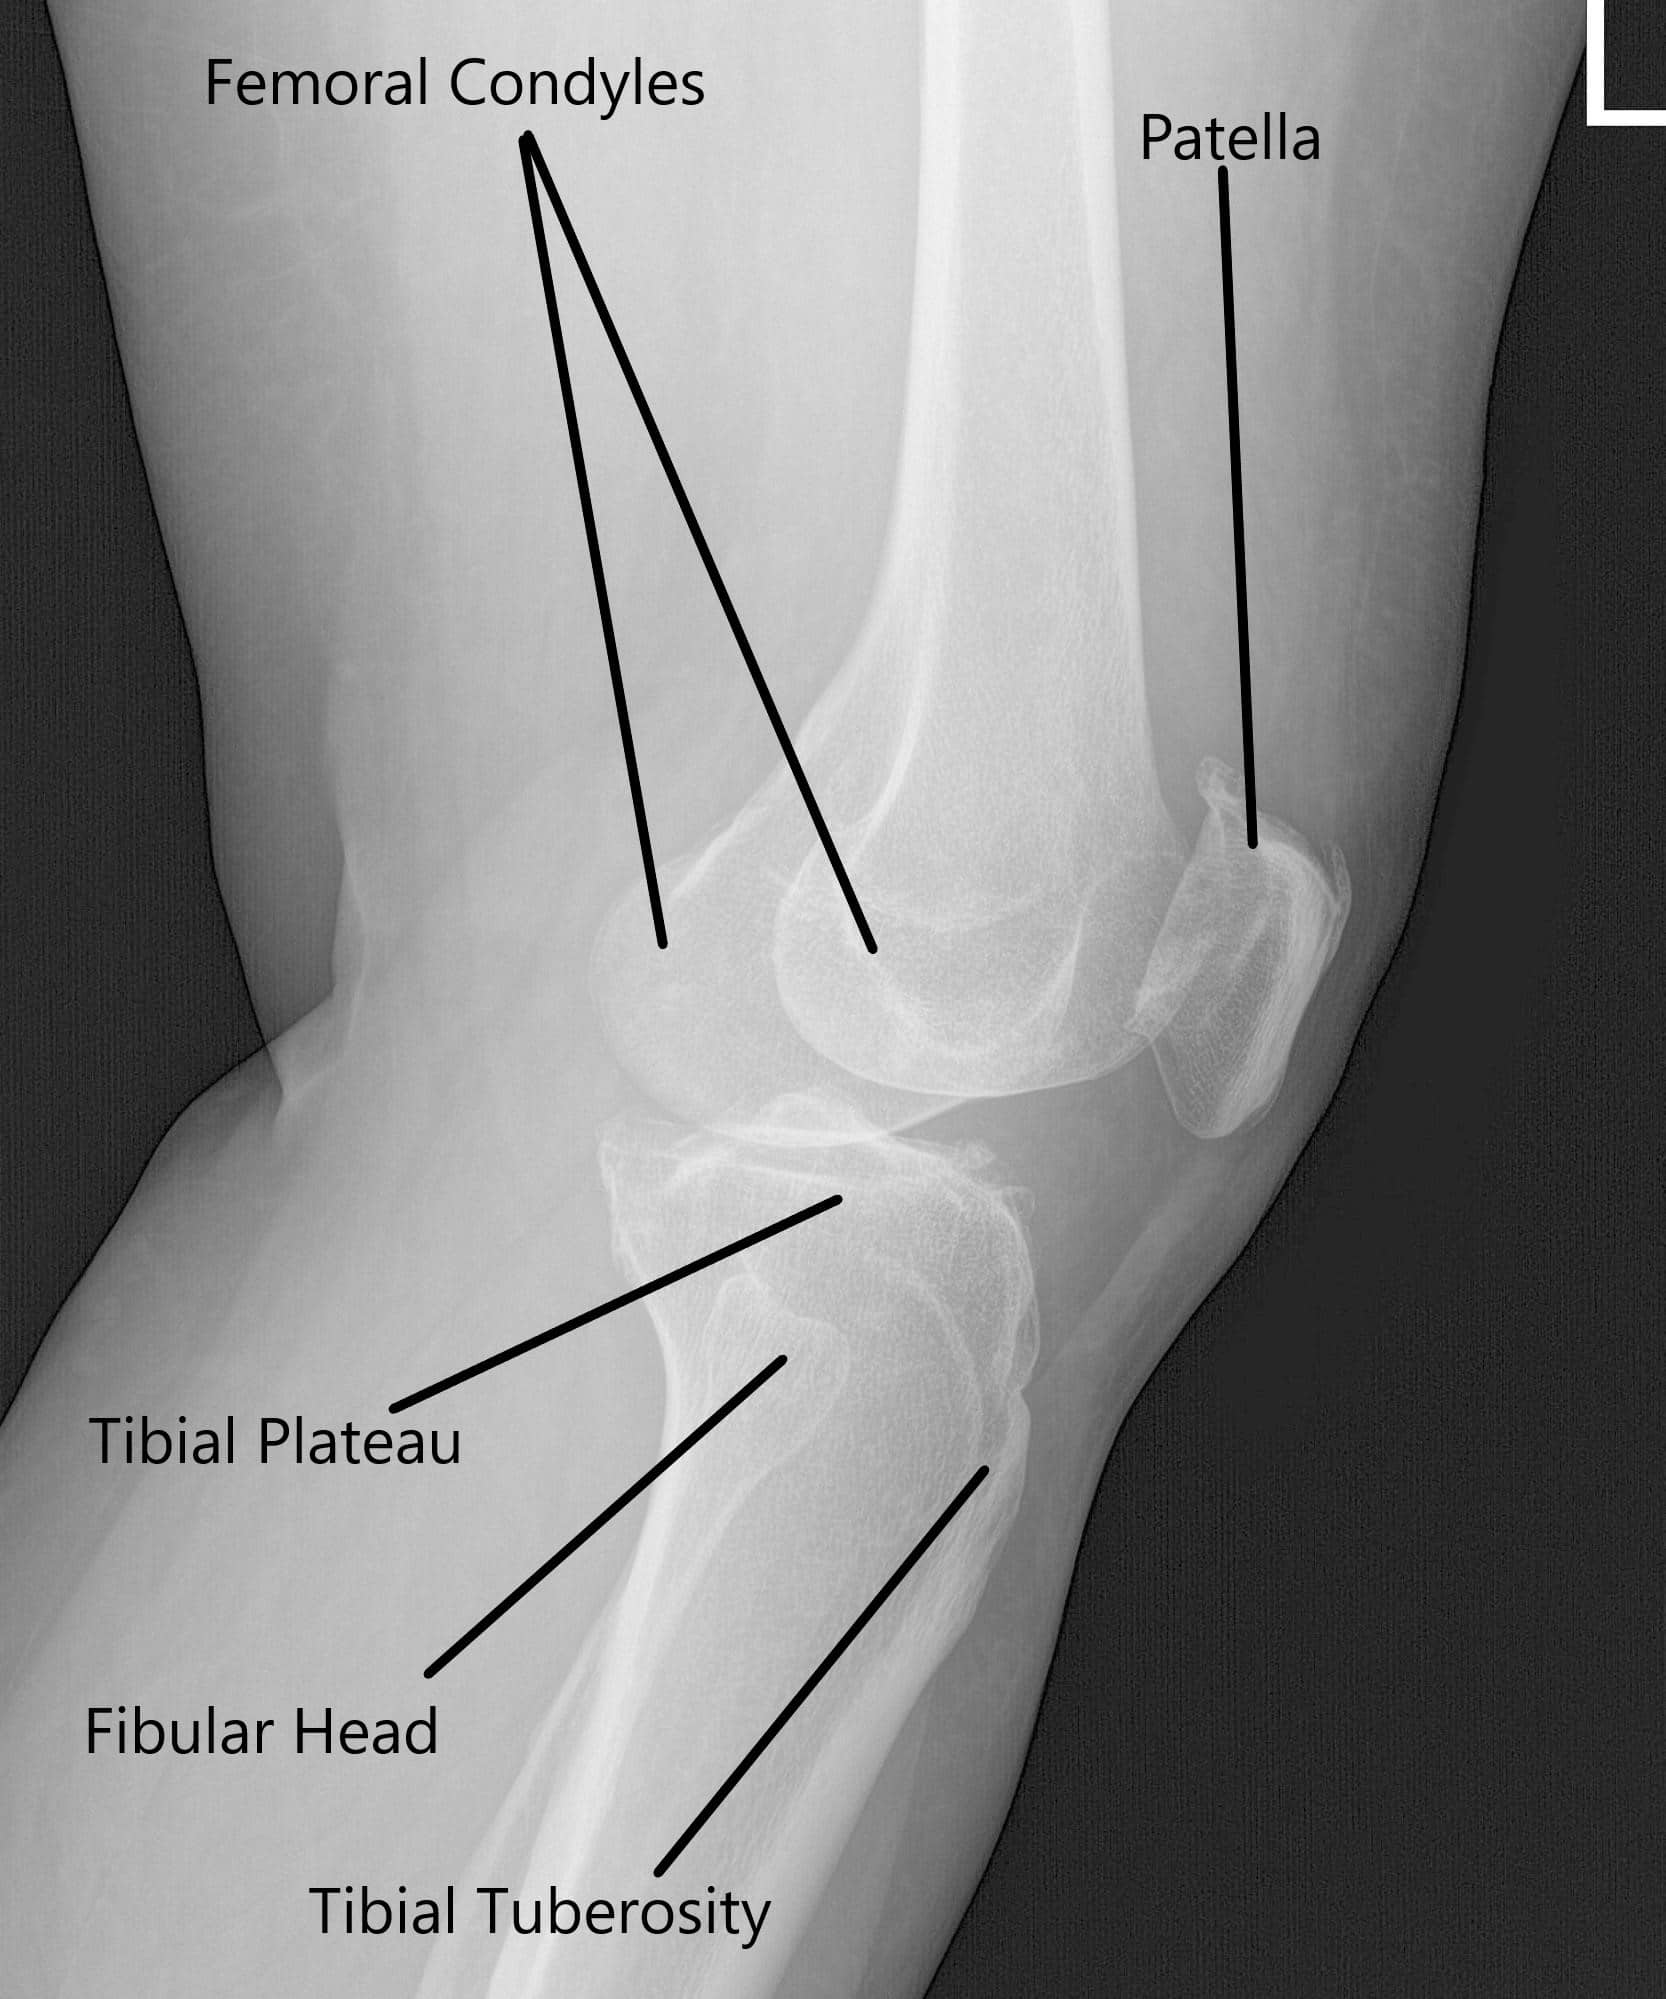

X-ray of the left knee showing AP and Lateral views.